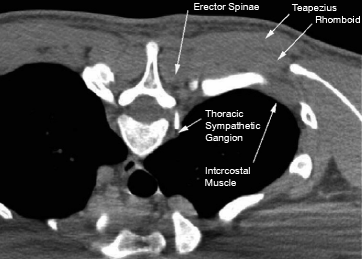

Trapezius muscle, large, superficial muscle at the back of the neck and the upper part of the thorax, or chest.

The trapezius can be divided into three bands of muscle fibers that have distinct structures and functions within the muscle. The muscle originates from the occipital bone as well as a cervical and thoracic vertebra. The trapezius is a large paired surface muscle that extends longitudinally from the occipital bone to the lower thoracic vertebrae of the spine and laterally to the spine of the scapula. Lateral clavicle, acromion and spine of scapula.